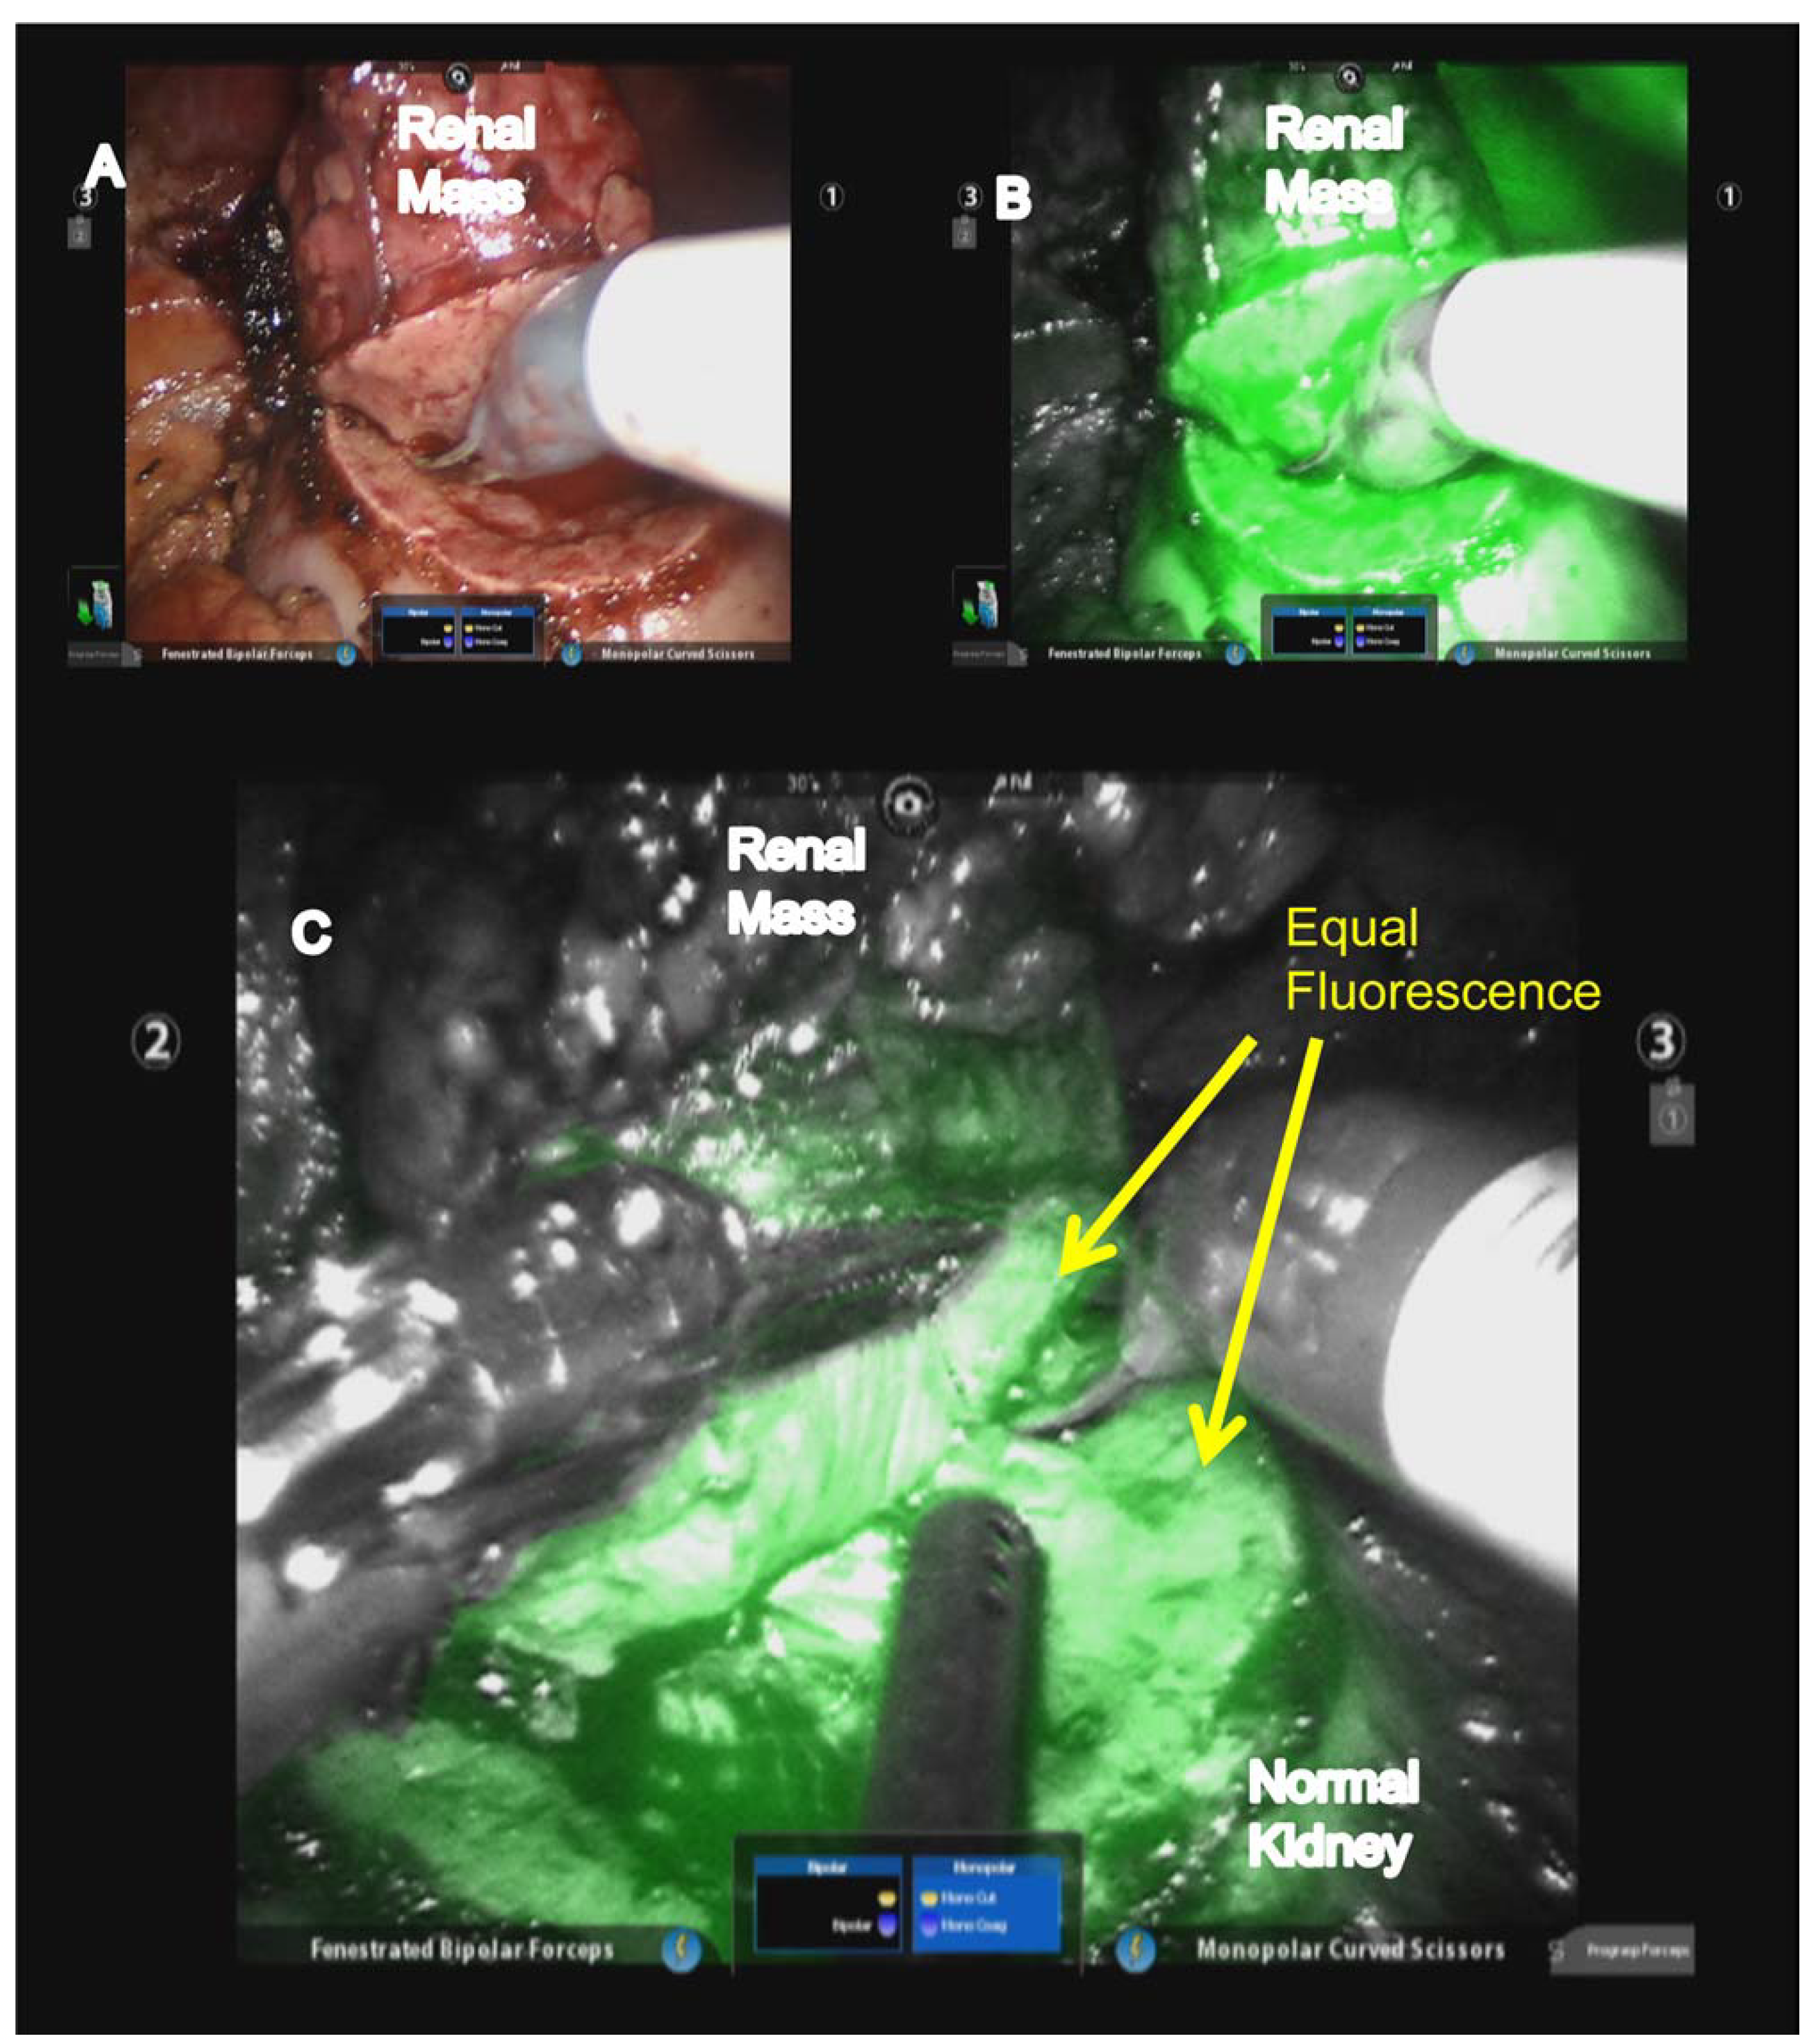

Figure 1.

Toggling between (A) white and (B) near infrared fluorescence (NIRF) to evaluate renal mass margins and (C) maintenance of equal fluorescence of normal renal parenchyma covering tumor and toward normal kidney. (Used with permission, Elsevier: Krane, L.S.; Manny, T.B.; Hemal, A.K. Urology 2012, 80, 110–118).